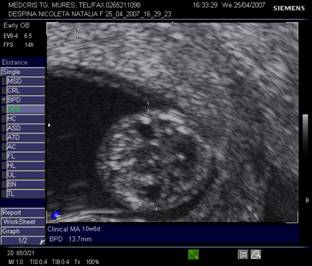

Fig. nr.128 Pliu nuchal cu dimensiunea de 2,9 mm.Cu sageata se remarca alaturat amniosul, magnificatia redusa nu permite obtinerea unei imagini optimale a translucentei nuchale.

Fig. nr.129 Masurarea pliului nuchal la o marire corespunzatoare

Masurarea NT egala sau peste 3 mm este considerata anormala. Riscul defectelor cromozomiale creste marcat in functie de marimea NT si de varsta mamei, necesitand punctie biopsie de vilozitati choriale sau amniocenteza.

Cea mai buna metoda de screening [18] ramane asocierea varstei materne, masurarea translucentei nuchale si nivelul seric matern de HCG β- human chorionic gonadotropin si PAPP-A (Pregnancy associated plasma protein- A) la 11 - 14 sapt gestationale ( dublu test ). Detectarea defectelor cromozomiale este in jur de 90%, cu ajutorul unui soft ce integreaza aceste date si efectueaza calculul riscului relativ.